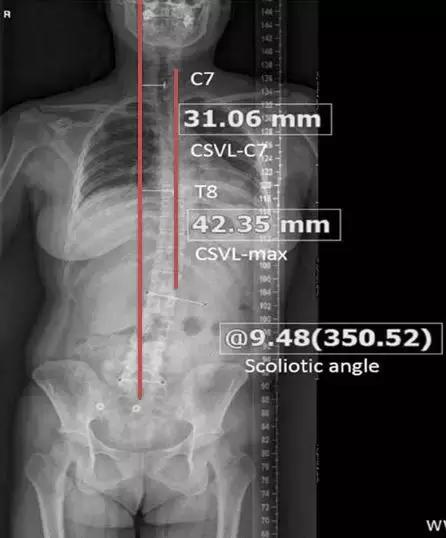

随后应该到医院拍摄全脊柱X线片(如下图右图)进行确诊,同时由专业医生进行测量,了解侧弯的幅度,如果成角超过10度,就可以诊断为脊柱侧弯了。

此外从影像上,还可以看出腰椎侧弯后,上半身重心的偏移情况。

如下图所示,患者的头部相对于臀部,朝着图中右侧的方向移位了。这个移位超过1cm就可以诊断为上半身重心偏移。